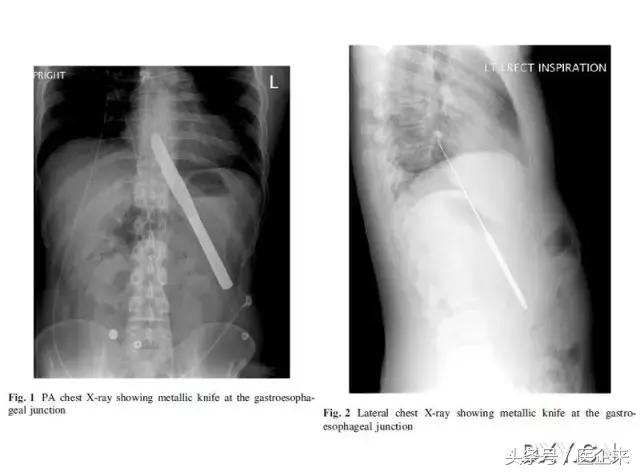

6. 经口吞下的餐刀(真的是饿到不行了吧...)